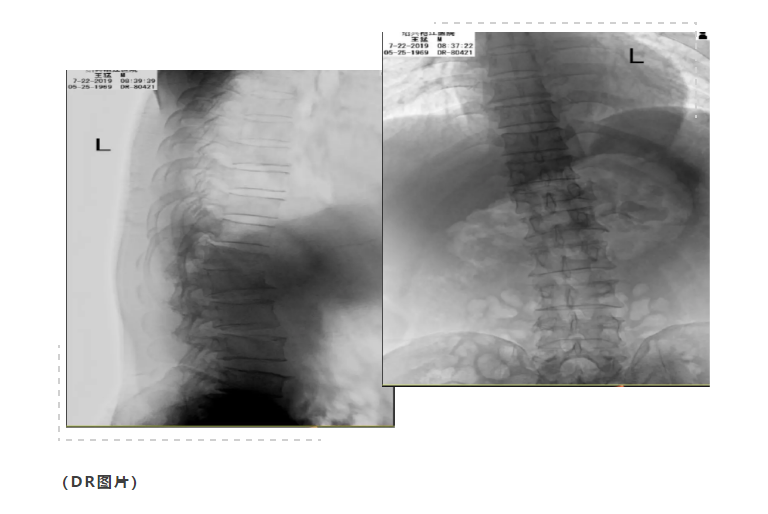

本院2019-07-22胸腰椎CT示:

胸椎第12胸椎压缩爆裂性骨折,骨片分离,椎管有狭窄,两侧附件骨折;第1腰椎轻度压缩性骨折,第1、2腰椎左侧横突骨折。第3腰椎前上缘骨折。

术后预防感染、消肿镇痛、营养神经、指导卧床活动锻炼等对症支持治疗,复查DR及CT示椎体高度恢复,椎管减压充分。